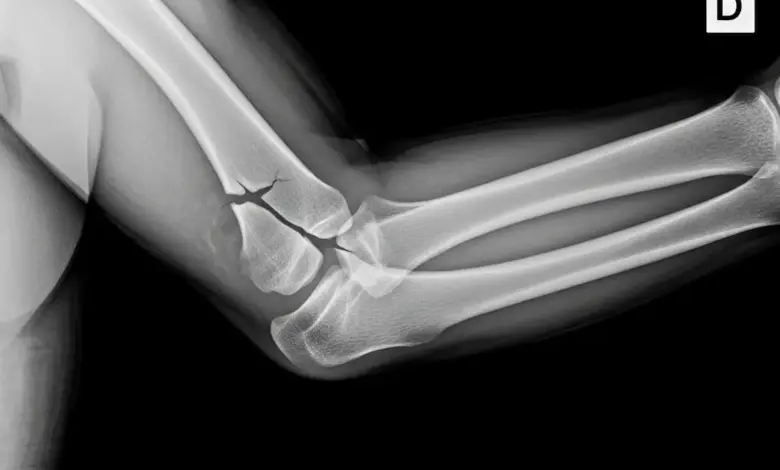

As radiografias em incidência anteroposterior e perfil costumam ser o primeiro exame. Só que, em fraturas sem desvio, o traço pode não aparecer.

Quando existe dúvida sobre quantidade de fragmentos, grau de desvio e planejamento cirúrgico, a tomografia costuma ser o exame mais útil.

- Desvio significativo.

- Múltiplos fragmentos.